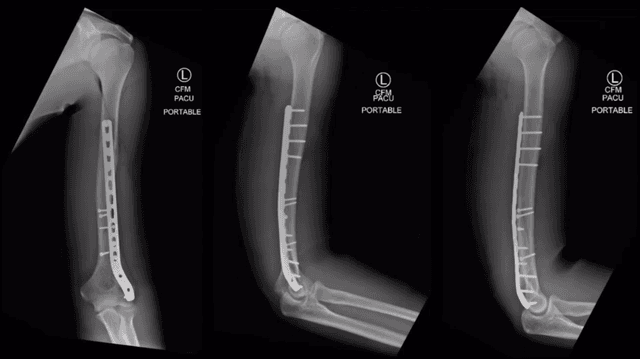

Imaging

Post-op